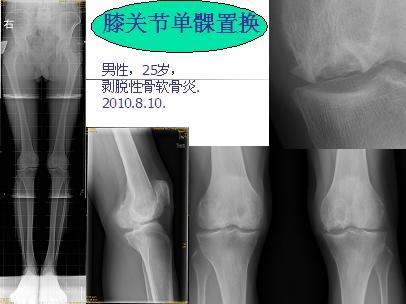

膝关节单髁置换

男性,25岁,行走疼痛2年。

术中见单髁破坏严重,病理为:剥脱性骨软骨炎